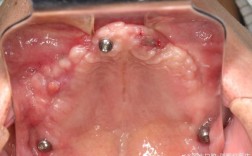

(图片来源网络,侵删) - 特定的牙齿位置: